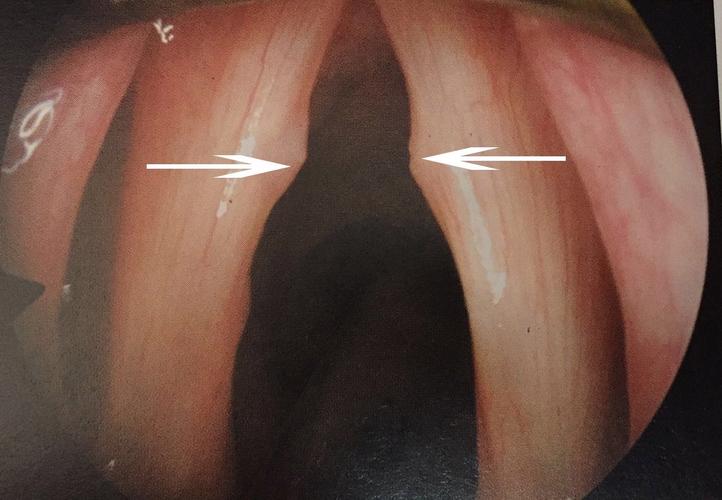

天天得靠嗓门吃饭的人,..老师、销售、歌手最容易中招。声音嘶哑、咳嗽个不停,成了这些人家常便饭。声带小结一出来,唱歌、说话都得小心翼翼,稍微不留神就咳个不停。